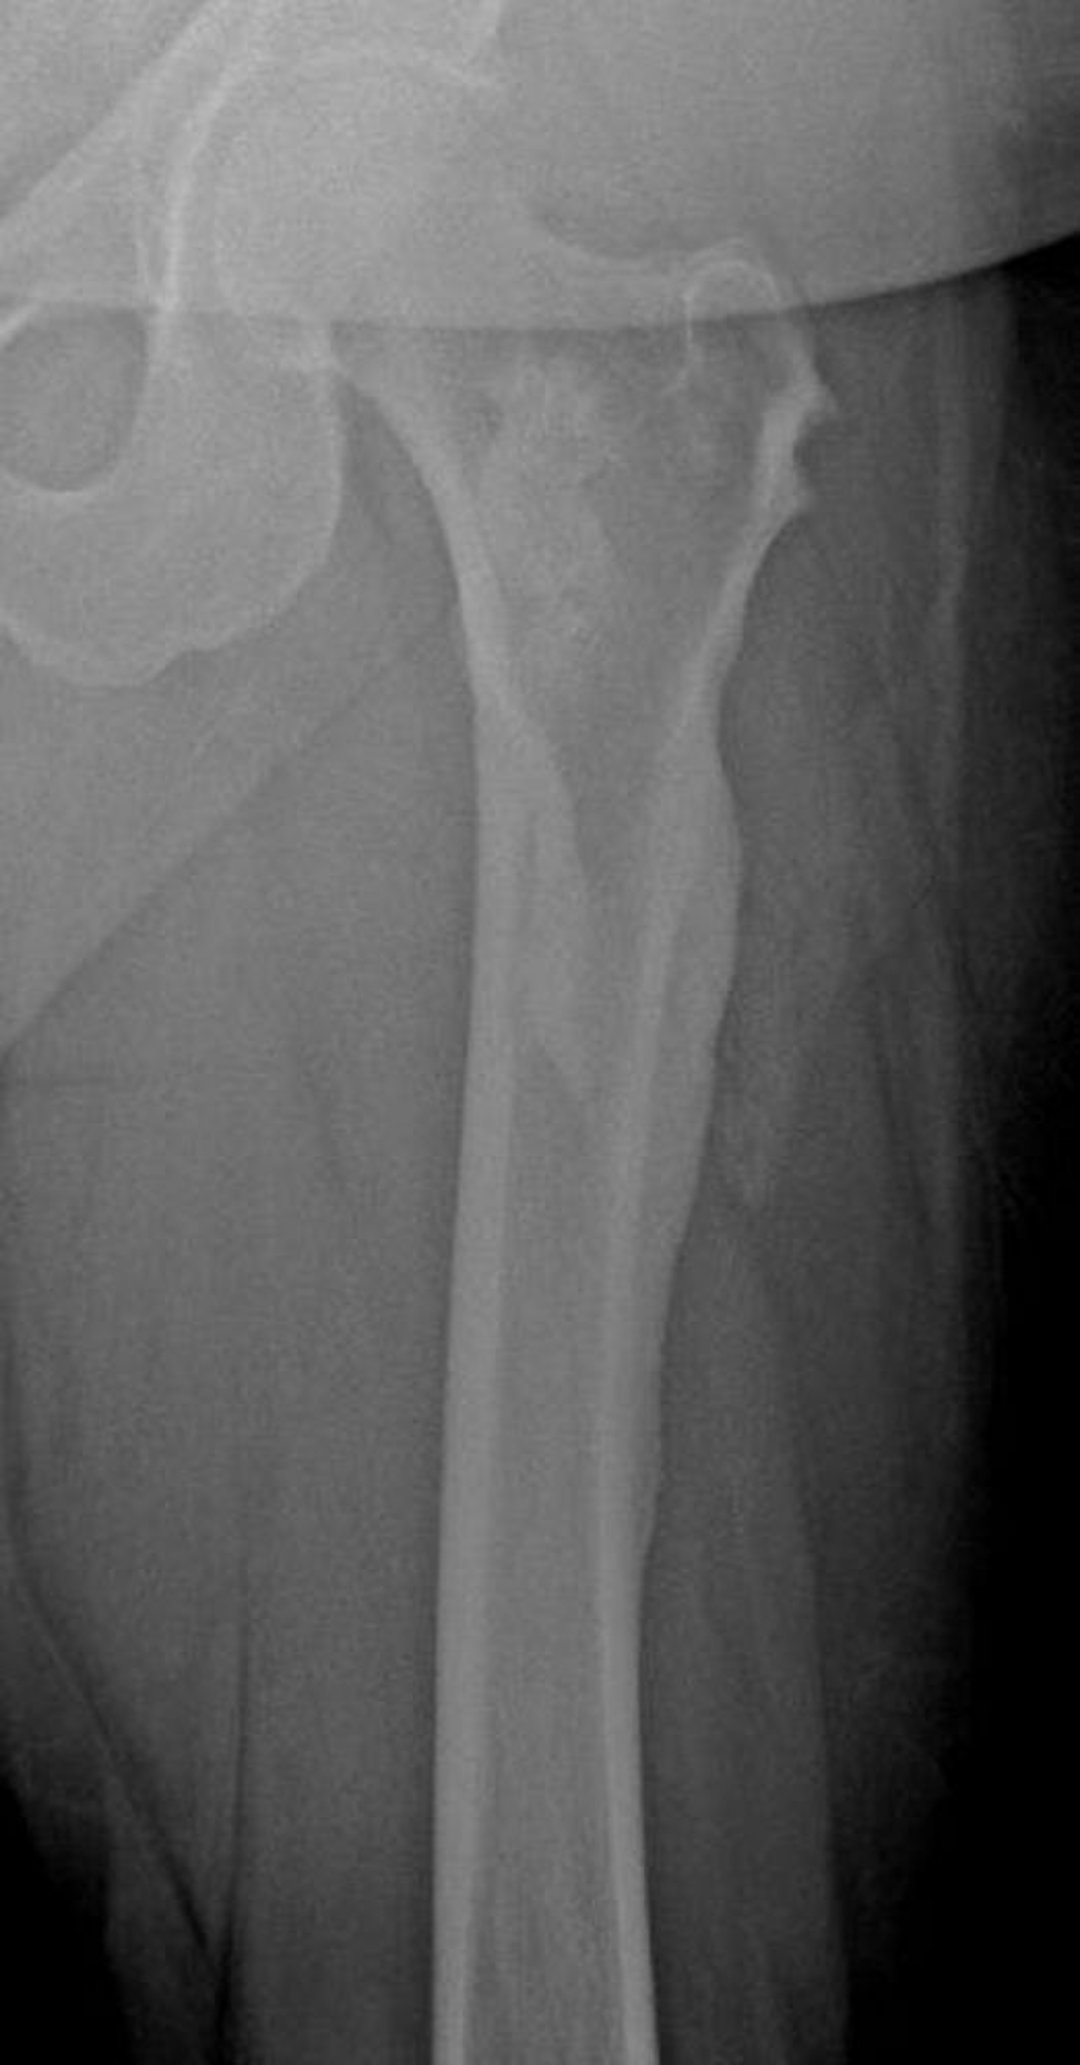

Bệnh nến xương (sáp nến nhỏ giọt)

Phim chụp X-quang này cho thấy biểu hiện hình ảnh "sáp nến nhỏ giọt" của bệnh nến xương ở xương đùi; hình ảnh này đặc biệt thấy rõ ở vỏ xương đùi ngoài.

Hình ảnh do bác sĩ Michael J. Joyce và bác sĩ David M. Joyce cung cấp.